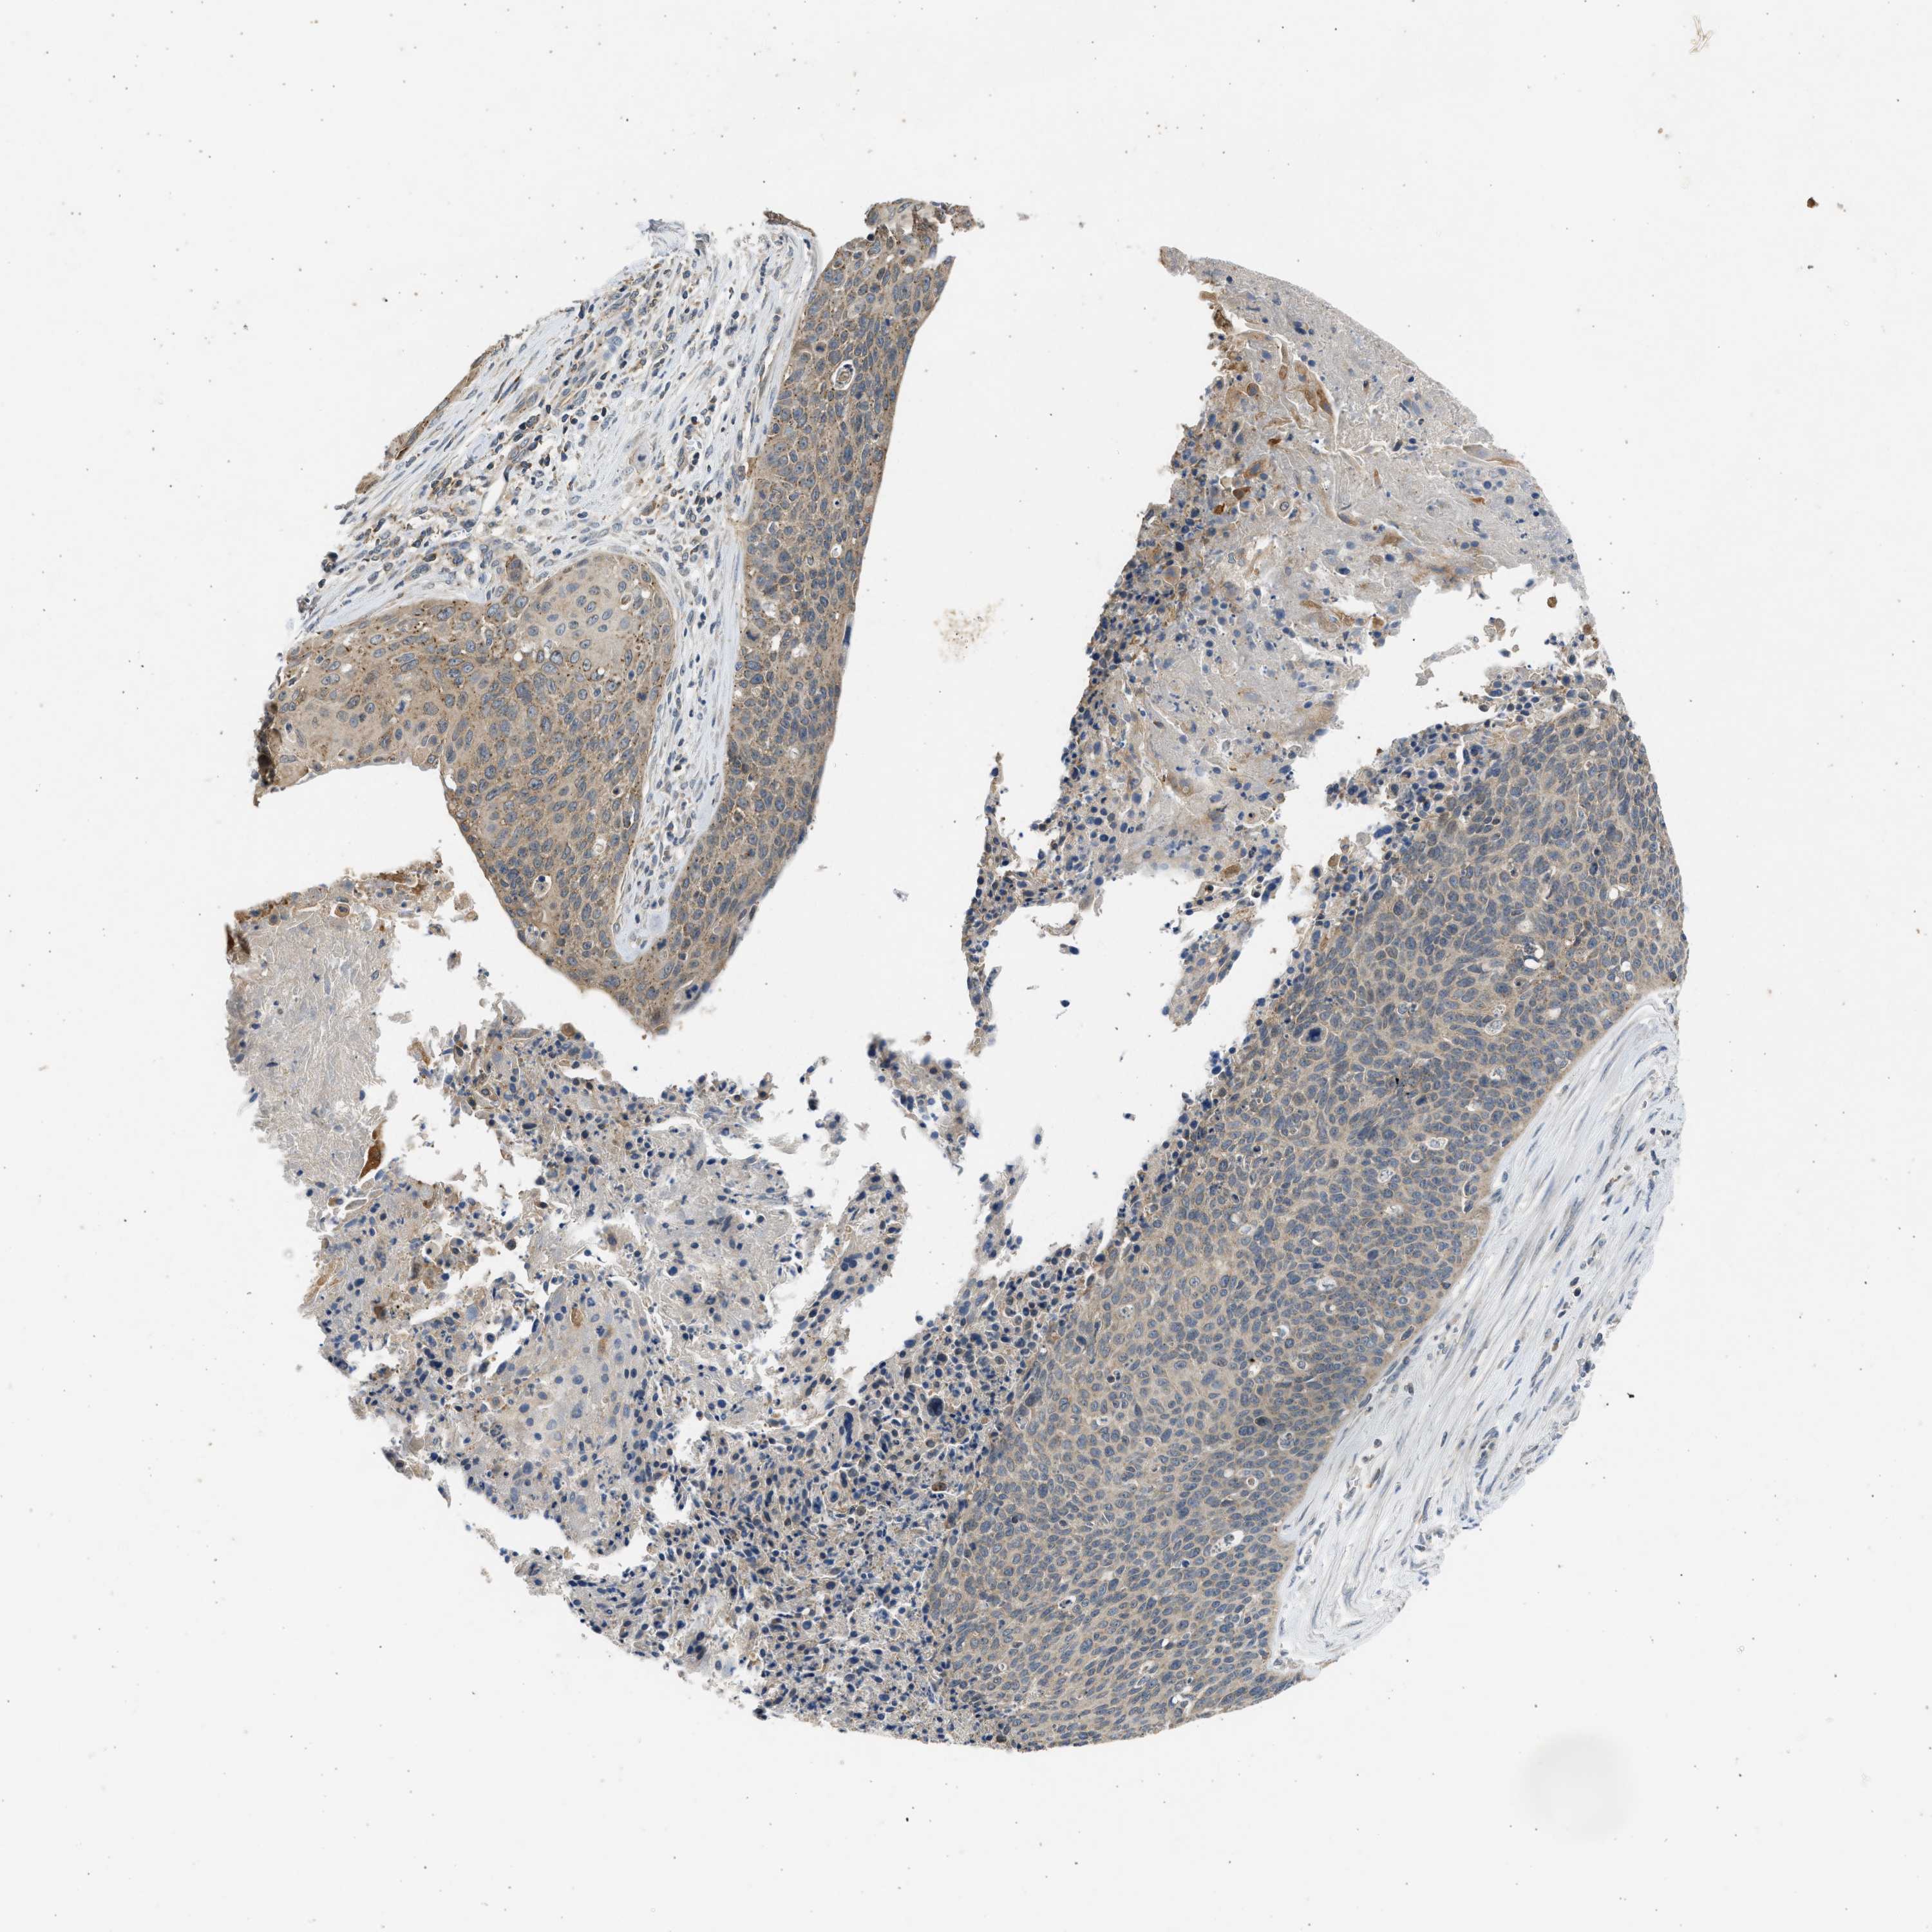

CERVICAL CANCER - Protein expressioni

A mouse-over function shows sample information and annotation data. Click on an image to view it in a full screen mode. Samples can be filtered based on level of antibody staining by selecting one or several of the following categories: high, medium, low and not detected. The assay and annotation is described here.

Note that samples used for immunohistochemistry by the Human Protein Atlas do not correspond to samples in the TCGA dataset.

Antibody stainingi

Antibody staining in the annotated cell types in the current human tissue is reported as not detected, low, medium, or high, based on conventional immunohistochemistry profiling in selected tissues. This score is based on the combination of the staining intensity and fraction of stained cells.

Each image is clickable and will lead to virtual microscopy that enables deeper exploration of all samples and also displays staining intensity scores, fraction scores and subcellular localization as well as patient and tissue information for each sample.

Antibody CAB018654

Staining

High

Medium

Low

Not detected

Intensity

Strong

Moderate

Weak

Negative

Quantity

>75%

75%-25%

<25%

None

Location

Nuclear

Cytoplasmic/membranous

Cytoplasmic/membranous,nuclear

Squamous cell carcinoma, NOS

Adenocarcinoma, NOS